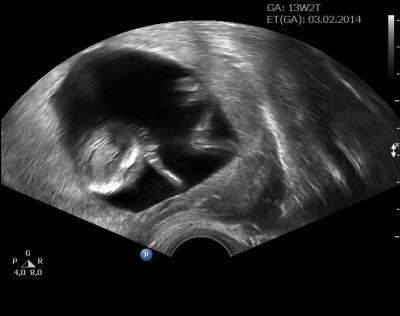

Hallo liebe Mitomis ich war heute mit meiner Tochter zum Ultraschall. Alles ist bestens unser kleiner Schatz entwickelt sich sehr gut ist nun 6,5 cm groß. Es kommt wohl ganz nach der Mama zumindestens was die Füße an geht, die sind ja schon riesig. Ich bin total verliebt

Bild zu Hin und weg - Forum und Treffpunkt für Omas